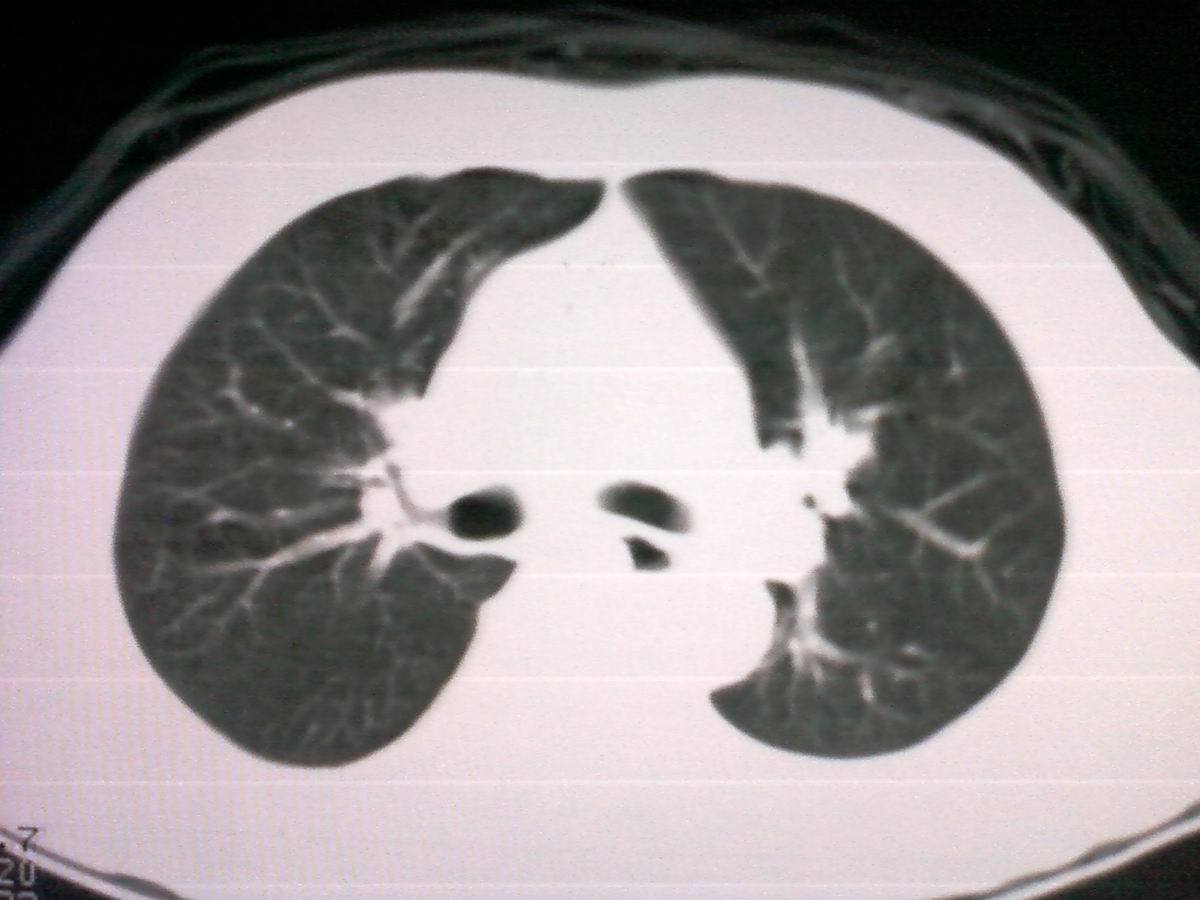

标题: CT25801:患者男性,65岁,临床提示双肺可闻及广泛罗音,看 [打印本页]

标题: CT25801:患者男性,65岁,临床提示双肺可闻及广泛罗音,看

仅见肺纹理影增重 纵膈淋巴结钙化